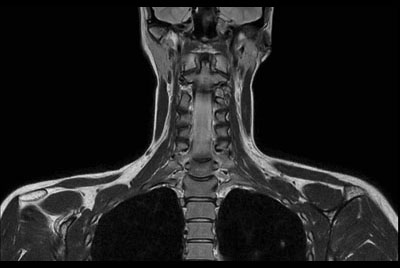

Neck stenosis